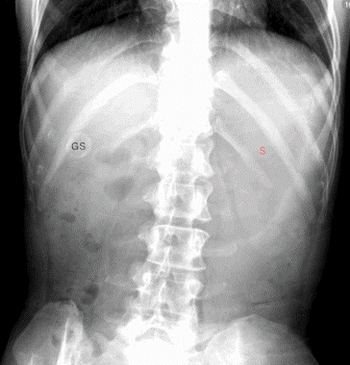

A 34-yr-old bed-bound woman with mental delay, cerebral palsy, and lower extremity paraplegia presented to the emergency department after 10 to 15 episodes of greenish-tinged vomit. Her caregivers reported that the she had been vomiting for the entire day. On physical exam, the patient’s abdomen was non-tender, non-distended, and had normal bowel sounds.